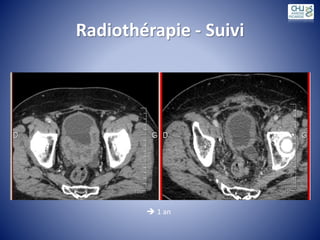

Radiothérapie - Suivi

 1 an